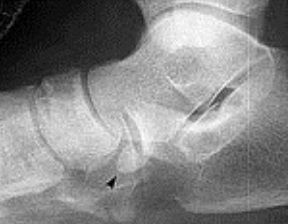

What disease is this? What does the arrow indicate? | Rheumatoid arthritis. Arrow = Bone erosion secondary to inflammation of retrocalcaneal bursa. |